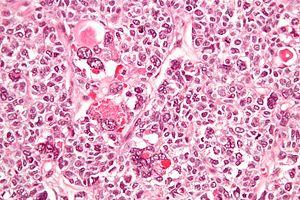

Micrograph of a juvenile granulosa cell tumour with hyaline globules. H&E stain.

Tumours vary in size, from tiny spots to large masses, with an average of 10 cm in diameter. Tumours are oval and soft in consistency. On cut-section, histology reveals reticular, trabecular areas with interstitial haemorrhage and Call-Exner bodies-small cyst like spaces interspersed within a graafian follicle.